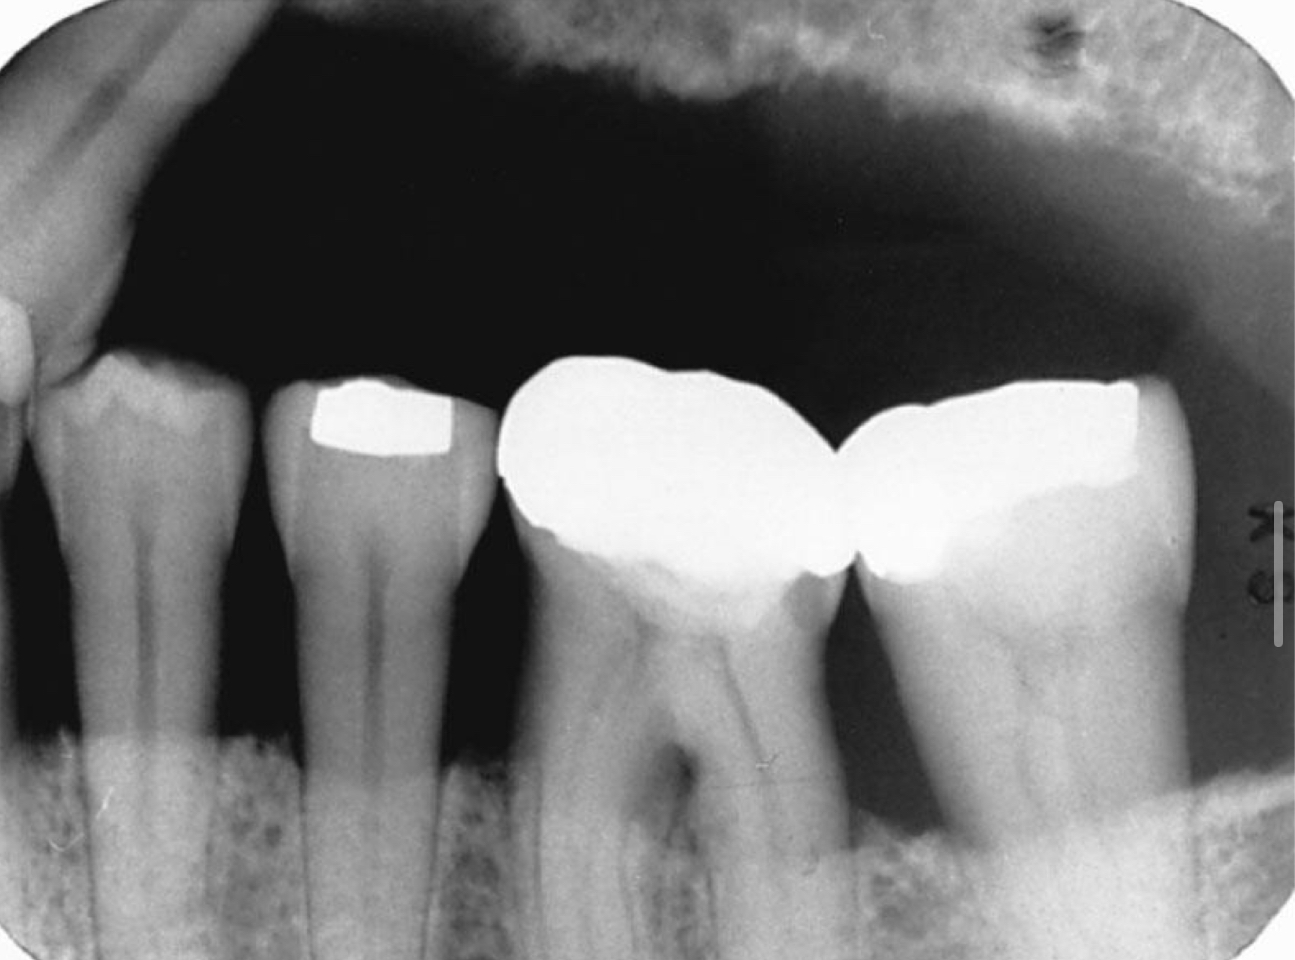

Preferred exposure method and film

PA with paralleling technique

Local irritants may contribute to: calc, defective restorations

Defective amalgam

Open contacts